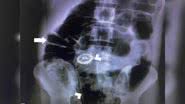

Homem já tinha histórico de inserir objetos inusitados no ânus